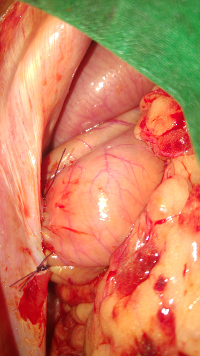

Chirurgies appareil urogenital :

-ovariectomie / ovariohysterectomie, castration, césarienne

-uretrostomie perineale scrotale chien chat

-nephrectomie

-chirurgie kystes prostatiques marsupialisations

Uretrostomie chien